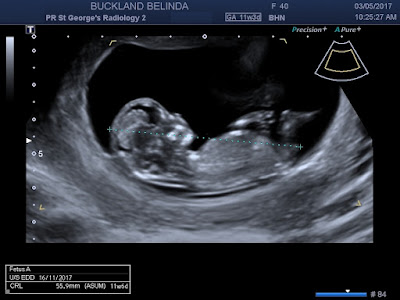

Officially 11 weeks 3 days, but I thought it would be more like 11 w 5 days. Baby is measuring 11 w 6 days. So doing well.

A cute photo where it looked like baby was sucking its thumb.

The 4D photo didn't work that well as the umbilical cord was handing right in front of baby's face.Still quite an incredible picture though.